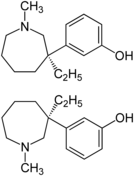

Others

Structures

| Other phenylpiperidines | |||

Picenadol Picenadol |